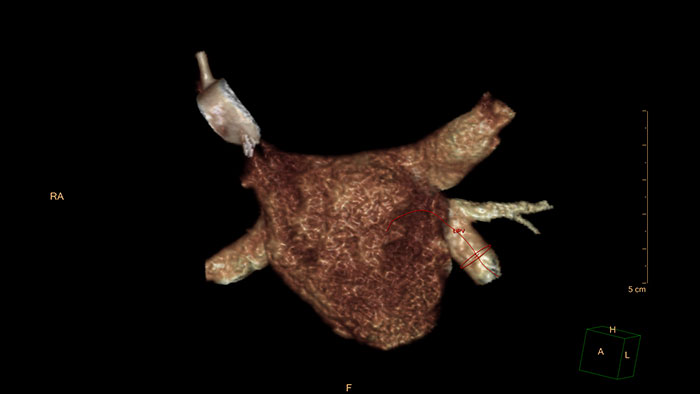

EP Planning

CT EP Planning

EP procedures planning

CT EP Planning allows electrophysiologists to quickly identify anatomy relevant to the EP procedure.

Benefits

• Provides, overall assessment of pulmonary veins, left atrial, and appendage anatomy, enabling the electrophysiologist to identify anatomy that may complicate the EP procedure.